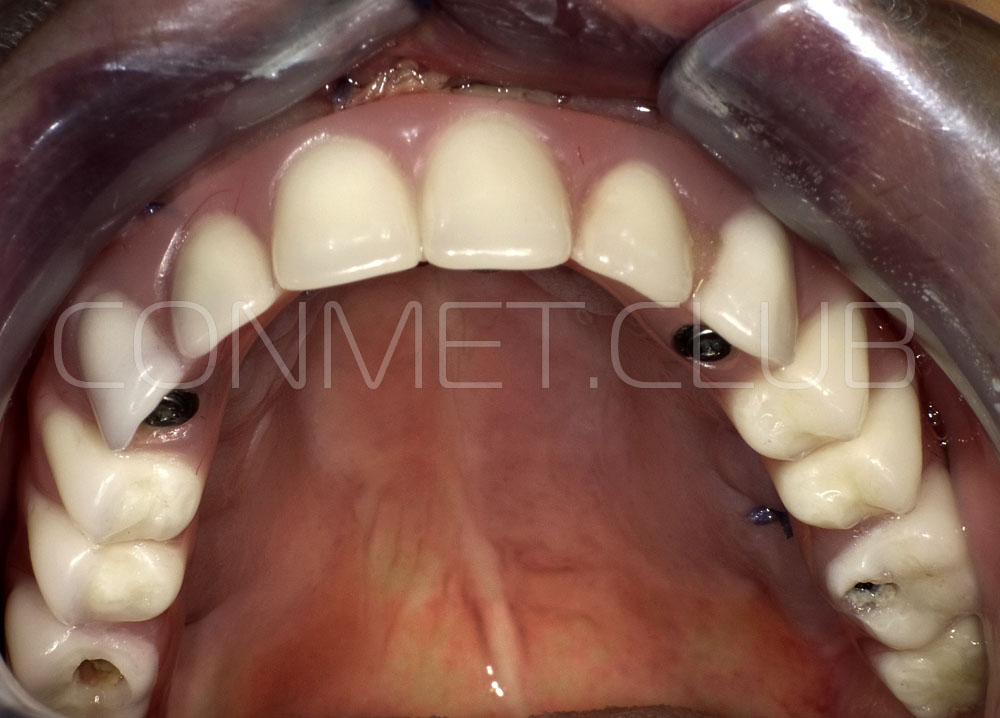

Новые, искусственные зубы фиксируются к этому имплантату стандартными, трансокклюзионными винтами на 1-14 день (в данном клиническом случае на 5 сутки) и по существу являются несъемными!

И в-четвертых: небольшой фрагмент из операции по восстановлению всех утраченных зубов на верхней челюсти. По сути эта операция полностью повторяет протокол и этапность операции представленной в первой части статьи, за исключением того, что искусственные зубы были зафиксированы сразу после операции. Со слов самой пациентки, процесс жевания был совершенно безболезненным с самого первого дня.